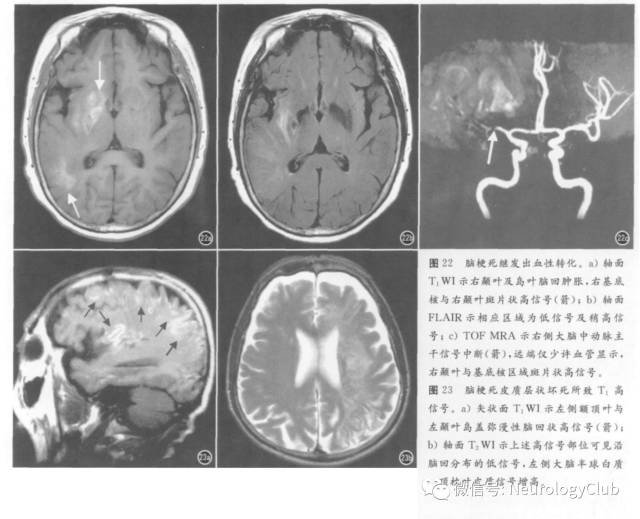

1. 脑梗死

脑梗死的短T1信号主要见于亚急性期,原因包括出血与皮质层状坏死,病理学基础为脱氧血红蛋白、高铁血红蛋白、铁、钙盐及其他顺磁性物质沉积。继发于抗凝治疗或再灌注所致的出血,称为出血性转化(图22),临床病例发生率高达43%,病理学发现率更高。T1WI高信号自发病第2天至2个月末均可出现。皮质层状坏死呈皮质线状或脑回状高信号(图23),见于2周后,1-2个月时最明显,可持续至第18个月,T2*WI及SWI序列研究表明并非出血,病理学上铁染色阴性,镜下显示为坏死碎屑中的蛋白变性,少数病例SWI序列上斑点状低信号可能代表顺磁性物质如锰与自由基沉积。多灶性出血性梗死提示为栓塞性,见于心内膜炎等。鉴别诊断包括肿瘤出血、静脉性脑梗死。

2. 缺血缺氧性脑病

也可出现短T1信号,但其脑皮质坏死选择性累及第4-6层,而脑梗死为全层坏死;脑梗死侵犯脑皮质突出的部分或称穹窿部,而缺血缺氧所致皮质坏死易见于脑沟处脑皮质,无囊状改变,但可发生铁沉积。